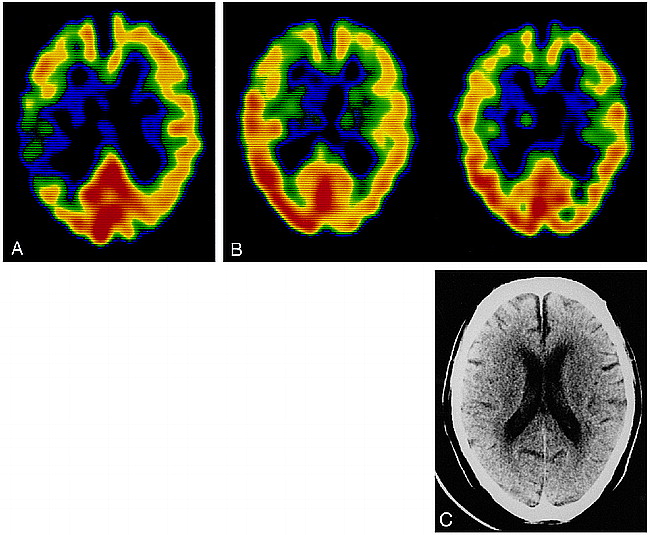

Case 1: 54-year-old man with atrial fibrillation and sudden onset of left-sided hemiparesis.

A, 99mTc-HMPAO SPECT image 4.5 hours after the onset of stroke shows hypoactivity in the right frontal and temporal lobes.

B, 99mTc-HMPAO SPECT image (left) obtained 12 hours after the initial study shows hyperactivity in the right temporal lobe; a 99mTc-ECD SPECT image (right) shows hypoactivity in the same area.

C, and D, CT scans after the SPECT study reveal a low-density area only in the right frontal lobe (C); 10 hours later, a partially hemorrhagic infarct has developed in the right temporal lobe (D).

Both sets of SPECT images depicted hypoactivity in the right frontal lobe. The 99mTc-HMPAO SPECT scans showed hyperactivity in the right temporal lobe, and the 99mTc-ECD SPECT scans showed hypoactivity in the same area (Fig 1B). Although a CT scan obtained after the SPECT study revealed a partial infarct in the right frontal lobe, low-density areas had not yet developed in the right temporal lobe (Fig 1C), and subsequent cerebral angiography showed partial recanalization of the lower trunk of the right middle cerebral artery (MCA). However, 10 hours later, the patient's motor functions rapidly deteriorated and a CT scan showed a partially hemorrhagic infarct in this area (Fig 1D).